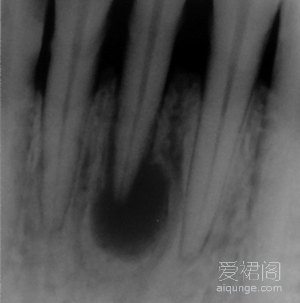

一个典型的根尖囊肿病例,对于这个患者来说,彻底的根管治疗是整个治疗过程的关键。首先,我们对这位患者进行了彻底完善的根管治疗,并要求患者在治疗过程中进行必要的抗炎治疗。患...